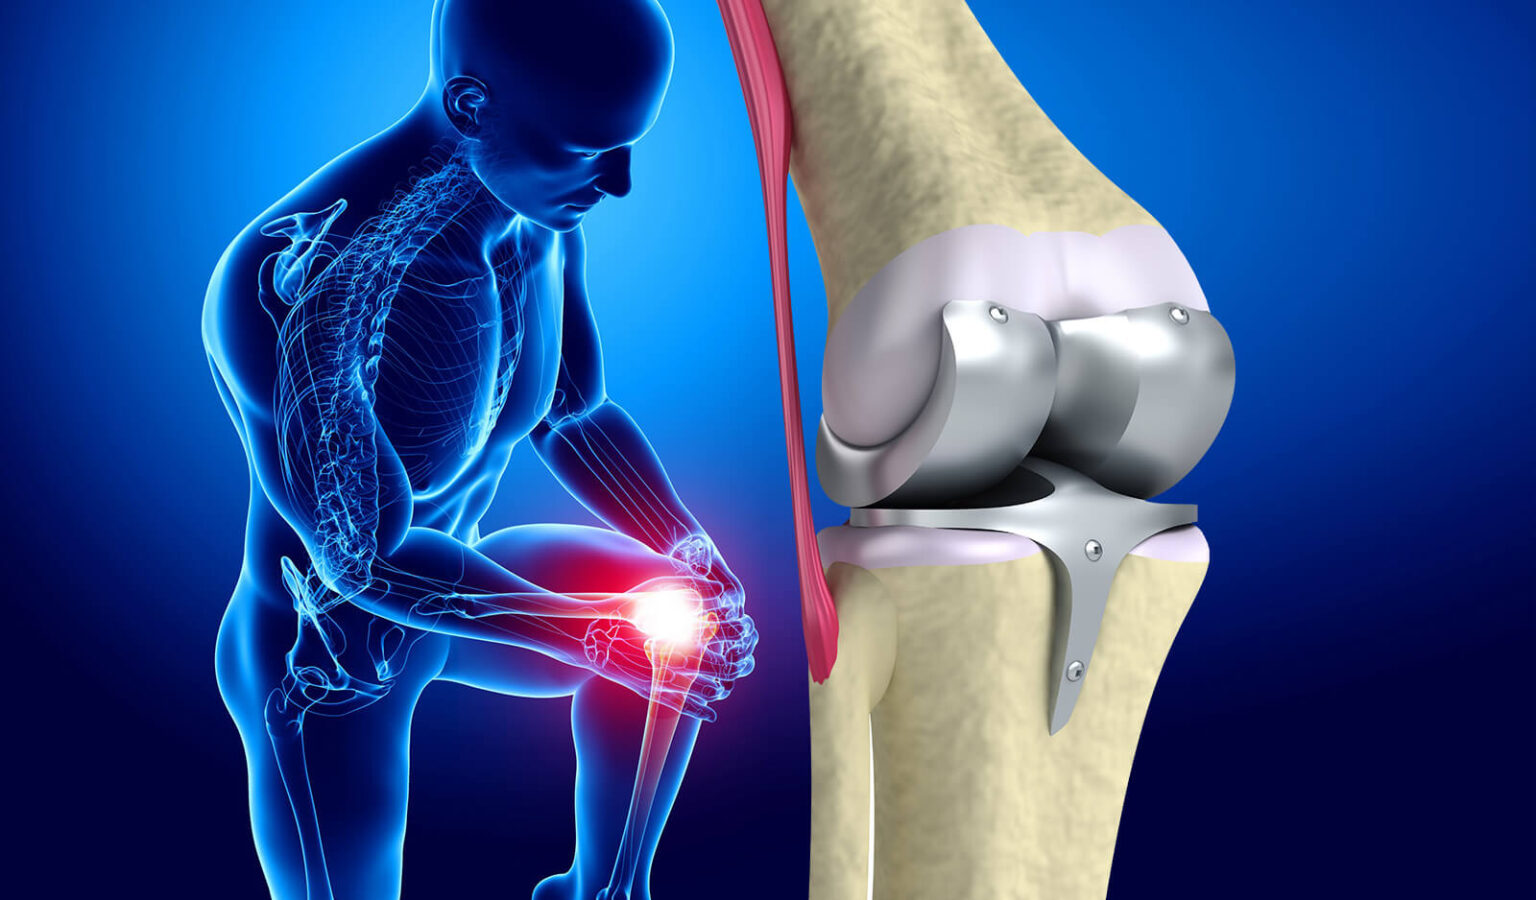

Фотографии и примеры протезирования коленного сустава